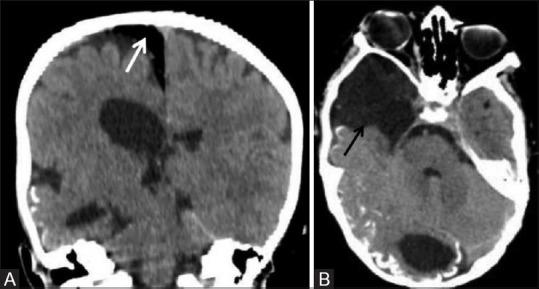

Phakomatoses or Neurocutaneous syndromes are a heterogeneous group of disorders and have variable inheritance pattern. Currently, more than 30 entities are included in this group. These disorders primarily affect the central nervous system; however, skin, viscera, and other connective tissues can also be involved with variable clinical presentation. We will describe and illustrate the various radiological findings of the common entities through the iconography of the cases presented to our department.

phakomatoses或神经皮肤综合征是一组异质性疾病,具有可变的遗传模式。目前,该组包括30多种疾病。这些疾病主要影响中枢神经系统;然而,皮肤、内脏和其他结缔组织也可能受累,临床表现各异。我们将通过提交至我科病例的影像学表现来描述和说明常见疾病的各种放射学表现。